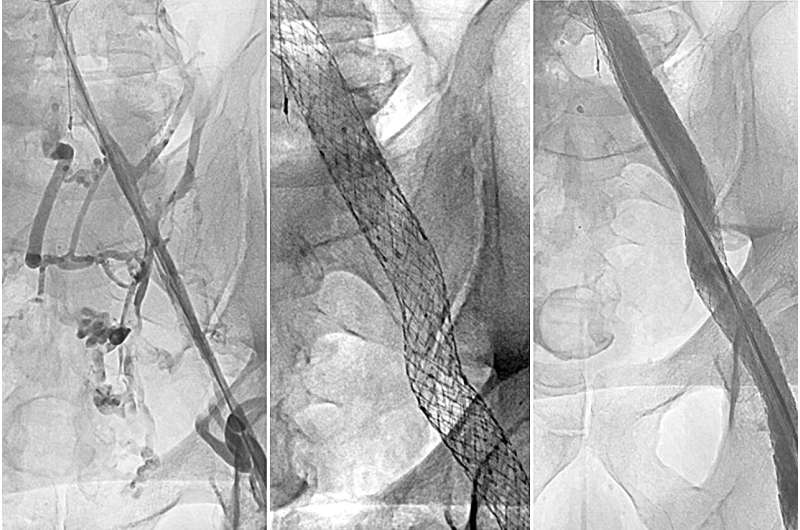

The study found that placing a stent to open and strengthen the affected vein reduced the severity of the post-thrombotic syndrome and improved venous symptoms and overall quality of life in affected patients.